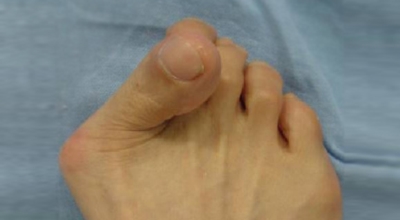

무지외반증은 발가락의 휘어짐 정도로 1단계 ~ 4단계까지 나눌 수 있어요.

1단계 : 15도 ~ 20도 휘어짐, 외관상 변화가 심하지 않음

2단계 : 20도 ~ 30도 휘어짐, 외관상 변화가 확연히 보임

3단계 : 30도 ~ 50도 휘어짐, 2, 3번째 발가락에 변형이 나타남

4단계 : 50도 이상 휘어짐, 정도가 심한 변형과 극심한 통증이 나타남, 정상적인 보행이 어려움

1, 2단계는 경증으로 통증이 나타나지 않으나, 3단계부터 신발을 신거나 쓸리고 눌릴 때마다 통증이 발생합니다. 4단계는 두번째 발가락이 엄지 발가락 위에 높아져 있다고 하며 뼈의 돌출이 심해진 상태라서 극심한 통증을 동반해서 신발을 신는 것 자체가 불편해지기도 합니다.